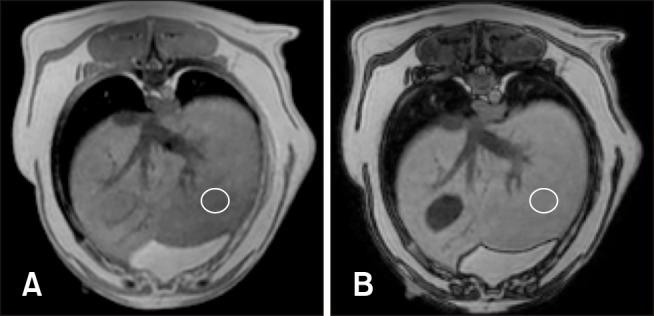

The objective of the present study was to describe two non-invasive methods for fat quantification in normal canine liver by using magnetic resonance imaging (MRI) and spectroscopy. Eleven adult beagle dogs were anesthetized and underwent magnetic resonance examination of the cranial abdomen by performing morphologic, modified Dixon (mDixon) dual gradient echo sequence, and proton magnetic resonance spectroscopy (H MRS) imaging. In addition, ultrasonographic liver examination was performed, fine-needle liver aspirates and liver biopsies were obtained, and hepatic triglyceride content was assayed. Ultrasonographic, cytologic, and histologic examination results were unremarkable in all cases. The median hepatic fat fraction calculated was 2.1% (range, 1.3%-5.5%) using mDixon, 0.3% (range, 0.1%-1.0%) using H MRS, and 1.6% (range 1.0%-2.5%) based on triglyceride content. The hepatic fat fractions calculated using mDixon and H MRS imaging were highly correlated to that based on triglyceride content. A weak correlation between mDixon and H MRS imaging was detected. The results show that hepatic fat content can be estimated using non-invasive techniques (mDixon or H MRS) in healthy dogs. Further studies are warranted to evaluate the use of these techniques in dogs with varying hepatic fat content and different hepatic disorders.

本研究的目的是描述两种使用磁共振成像(MRI)和波谱学对正常犬肝脏脂肪进行定量分析的非侵入性方法。11只成年比格犬接受麻醉,通过形态学、改良狄克逊(mDixon)双梯度回波序列和质子磁共振波谱(H MRS)成像对颅腹部进行磁共振检查。此外,还进行了肝脏超声检查,获取了肝脏细针穿刺抽吸物和肝活检组织,并测定了肝脏甘油三酯含量。所有病例的超声、细胞学和组织学检查结果均无异常。使用mDixon计算的肝脏脂肪分数中位数为2.1%(范围1.3%-5.5%),使用H MRS计算的为0.3%(范围0.1%-1.0%),基于甘油三酯含量计算的为1.6%(范围1.0%-2.5%)。使用mDixon和H MRS成像计算的肝脏脂肪分数与基于甘油三酯含量计算的结果高度相关。检测到mDixon和H MRS成像之间存在弱相关性。结果表明,健康犬肝脏脂肪含量可通过非侵入性技术(mDixon或H MRS)进行估计。有必要进一步研究评估这些技术在肝脏脂肪含量不同和患有不同肝脏疾病的犬中的应用。